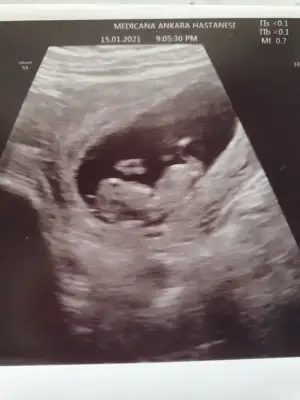

Tahmin konusunda yardımcı olursanız çok sevinirim.

Eklentiler

• 20210116_095242.webp

20210116_095242.webp

21,9 KB · Görüntüleme: 75